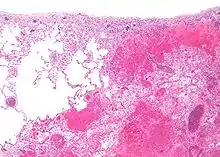

| Micrograph of a pulmonary infarct (right of image) beside relatively normal lung (left of image). H&E stain. | |

- Red infarctions (hemorrhagic infarcts) generally affect the lungs or other loose organs (testis, ovary, small intestines). The occlusion consists more of red blood cells and fibrin strands. Characteristics of red infarcts include:

- loose tissues that allow blood to collect in the infarcted zone

- tissues with a dual circulatory system (lung, small intestines)